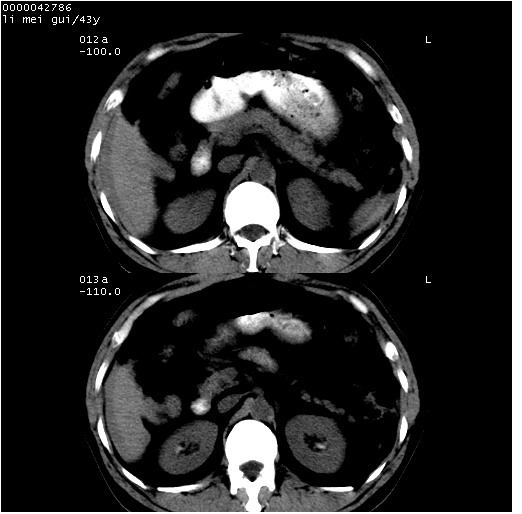

| 患者,男,43岁。突发腹痛2小时,面色苍白,难以平卧。自述近期无明确外伤史,为摩托车驾驶员。 腹部b超检查:脾脏中上极回声异常,肿瘤待排。 临床诊断:腹痛原因待查。 上中腹部ct轴位平扫+增强扫描(层厚10mm,螺距1.0,重建间隔10mm),图像如下: ![]() ![]() ![]() ![]() ![]() ![]() ![]() ![]() ![]() ![]() ![]() ![]() ![]() ![]() ![]() ![]() ![]() ![]() ![]() ![]() ![]() ![]() ![]() ![]() ![]() ![]() ![]() ![]() ![]() ![]() ![]() ![]() ![]() ![]() ![]() zrs发言:支持脾破裂 wwp发言:支持脾破裂并腹水。 xulianj发言:脾脏肿瘤破裂可能性大 zsl6918发言:不像肿瘤出血,考虑还是与外伤后引起的慢性出血有关 zzyy发言:平扫见肝周及脾周积液,脾内密度不均。脾内肿瘤较少见。还是外伤性脾破裂。 沈丘东方医院发言:脾门区一个不均匀强化病灶与其周液体相连多考虑脾占位破裂出血 yixianman001011发言:脾破裂并腹水是可以肯定的,具体原因多以肿瘤性破裂出血,脾脏淋巴瘤可能性大. 结果: 术后,经详细询问患者,其仔细回忆:一月前骑摩托时左侧腰部与别人有“轻微”触碰,因责任在自已,当时又无明显不适,未引起注意。 临床术后诊断:脾破裂并失血性休克(1.外伤性迟发性脾破裂。2.脾脏肿瘤破裂?) 术后标本病检:脾破裂并出血,未见明显肿瘤成份。 原贴地址:http://www.radinet.com.cn/forum_view.asp?forum_id=4&view_id=34070 |